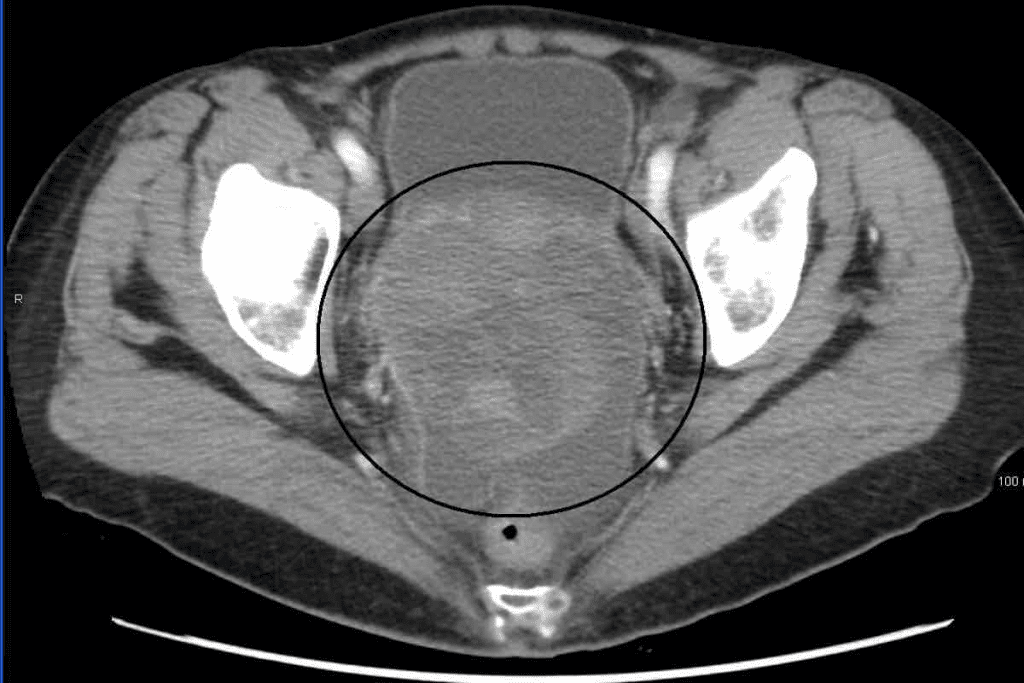

Normal Uterine Appearance on CT Imaging

The normal uterus shows clear signs on CT scans. These signs help doctors spot any problems. It’s important to know what a normal uterus looks like on a CT scan.

Homogeneous Enhancement Patterns After Contrast

A normal uterus shows a homogeneous enhancement pattern after contrast. This means the uterus gets contrast evenly. This evenness shows the uterus is healthy and working properly.

Zonal Anatomy Visualization

A normal uterus also shows clear zonal anatomy on CT scans. The uterus has layers like the endometrium, myometrium, and serosa. These layers are visible after contrast, helping doctors check their thickness and health.

Baseline Measurements and Characteristics

It’s key to know the baseline measurements and characteristics of the uterus. This includes its size, shape, and where it sits. These details help doctors see if anything changes over time.